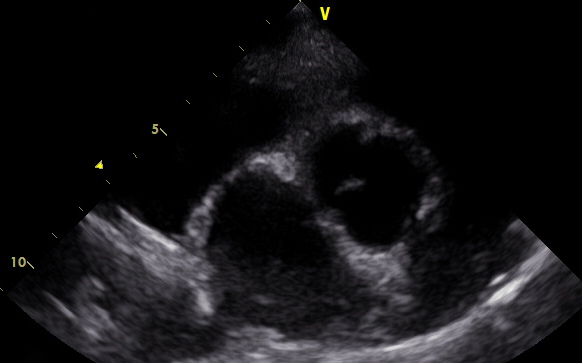

Es gibt verschiedene Ursachen für diese Form der Arrhythmie, welche mit Hilfe einer Echokardiographie weiter abgeklärt werden können. Daher wurde dem Besitzer als nächster diagnostischer Schritt ein Herzultraschall angeraten. Hierfür liegt der Hund auf einem speziellen Tisch und wird in rechter und linker Seitenlage geschallt. Im Herzultraschall zeigte sich in den Phasen, in denen „Astor“ die Rhythmusstörung hatte, eine stark verminderte Pumpleistung des linken Ventrikels mit einem subjektiv vergrößerten linken Herz (Hauptkammer und Vorkammer). Was sich dann auch in den Messwerten bestätigte. In Phasen, in denen der Herzschlag einen normalen Rhythmus hatte, war die Pumpleistung etwas besser, die Messwerte lagen im Graubereich. Der linke Vorhof war leicht vergrößert. Neoplasien oder Veränderungen im Herzmuskel konnten nicht dargestellt werden.

Ende Mai wurde dann „Astor“ erneut zur Ultraschallkontrolle vorgestellt. Ihm ging es nach wie vor gut. Im Ultraschall zeigte sich eine deutlich verbesserte Pumpfunktion des linken Ventrikels. Alle Messwerte lagen wieder im Referenzbereich. Eine weitere Untersuchung im August zeigte stabile Werte.